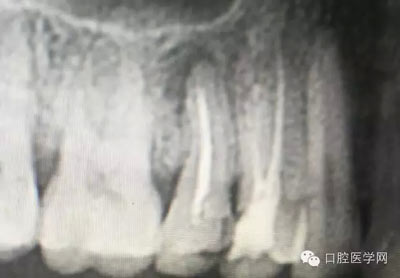

幾例根管再治療病例

深齲或者是齲壞備洞的時候意外穿髓,我們怎么處理好些?后期出現(xiàn)的牙髓的癥狀,是我們操作的問題?比如細菌層的存在,我們沒有清理干凈?還是我們窩洞沒有進行消毒,或者是隔濕沒有做好導致的粘結(jié)出現(xiàn)問題,還是材料充填的時手法不對,導致的材料收縮過大,還是我們的光照設(shè)備出現(xiàn)了老化沒有完全達到想要的固化,還是懸空的釉質(zhì)沒有去除導致的微滲漏的發(fā)生,或者是材料本身對牙髓產(chǎn)生的刺激,還是材料選擇的問題,或者是我們對材料的性能和說明沒有足夠的了解導致的,沒有按照材料的要求去做,還是我們自身對牙齒情況的判斷出現(xiàn)的問題......